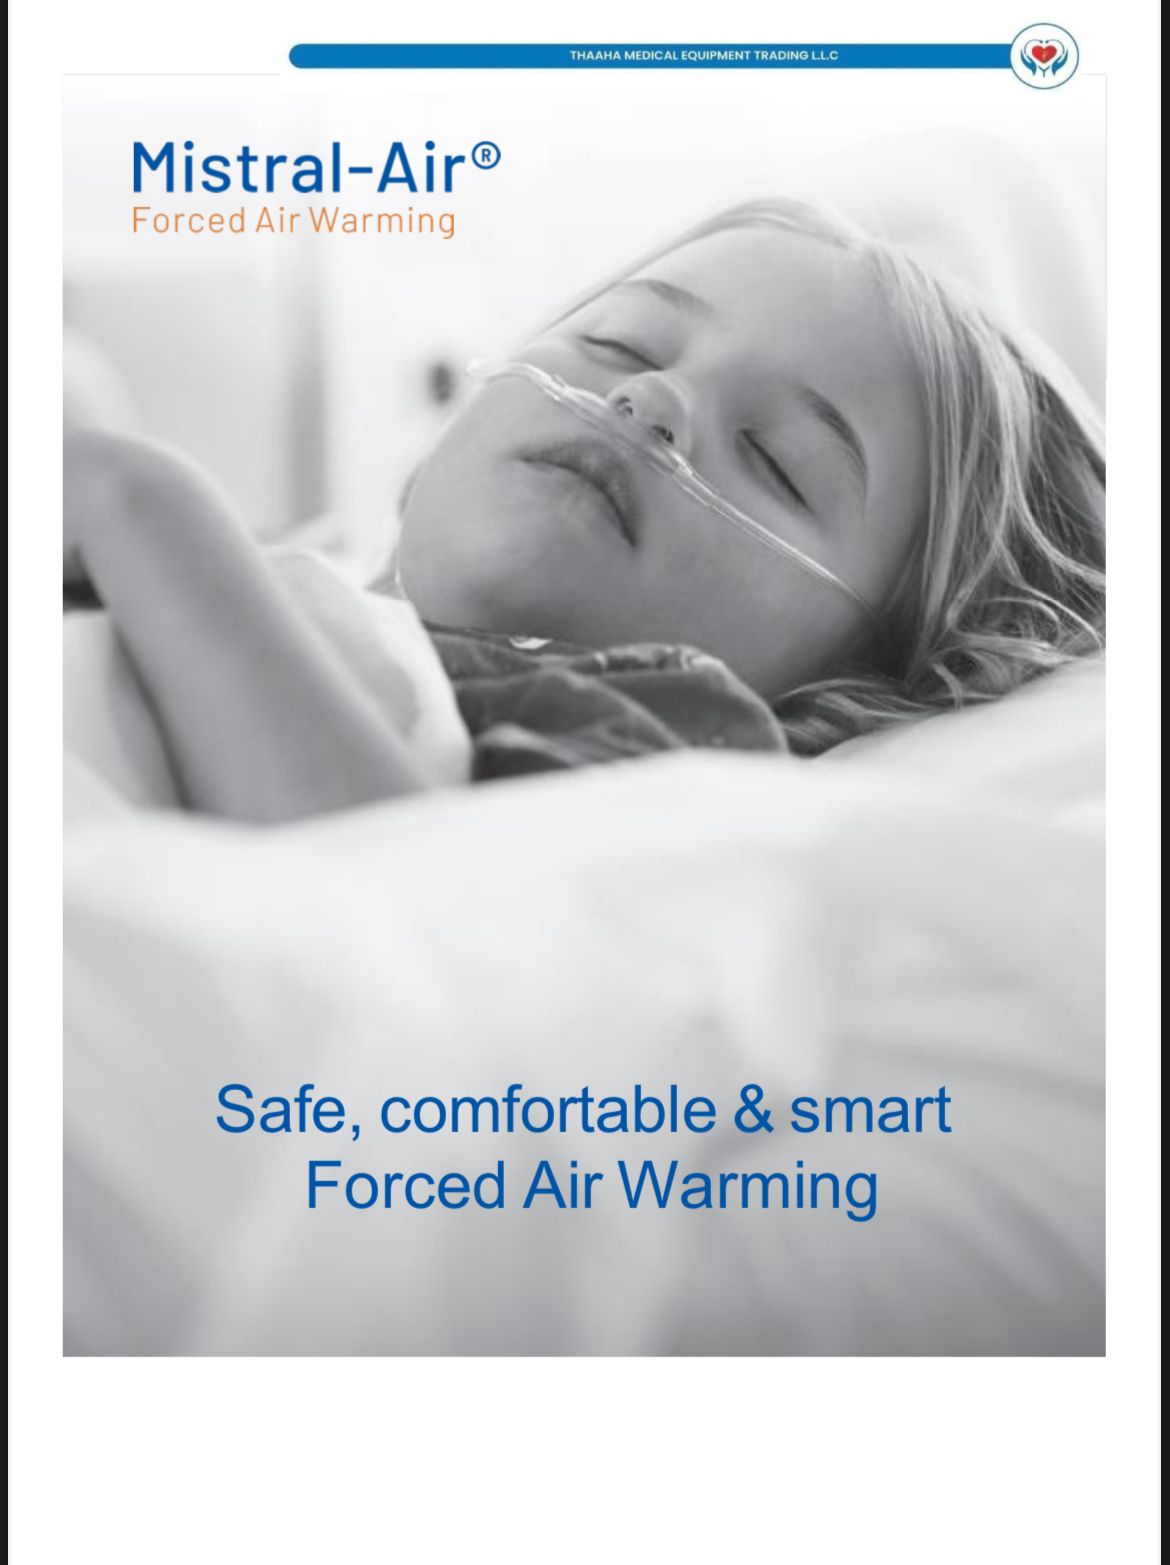

PATIENT WARMER

PATIENT WARMER